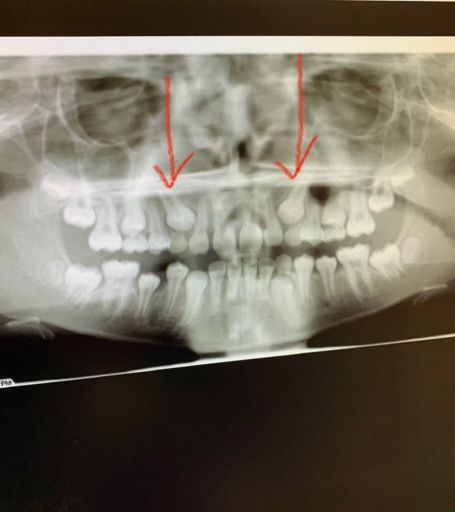

Hi, I have a frenulum on the right side of my mouth. It connects to my gums about 1cm behind the upper and lower back molars. It has become tight and painful. Have you ever seen anything like this? Is it safe to have it cut? I will attempt to add a photo. Thank you, H. Jay Graber

A frenum or frenulum is a small fold of tissue that restricts and secures the motion of a mobile organ. I have not heard of a frenulum in the back of the mouth. It would be best to bring this to the attention of your dentist, especially because it is causing discomfort. I did not see a picture attached to your question, however I am wondering if it is part of your cheek or possibly an impacted tooth that may be causing this discomfort. Use warm salt water rinses several times a day to soothe the tissues until you have a proper exam and diagnosis.

A frenulum or frenum is a small fold of tissue that restricts or secures the motion of a mobile organ. I have not seen a fold of tissue (unless sutured) that connects distal to the molars. There is a frenum that connects your tongue to the floor of your mouth as well as one that attaches your lips to your jaws. Since you are experiencing pain, it is important for you to see your dentist immediately to be sure you do not have an infection or a tooth that is creating swelling in the area.